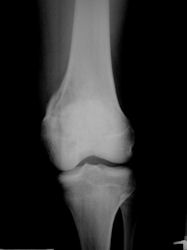

- Distal Femur: most common site (40%; about twice as common as proximal tibia)

- Proximal Tibia: Second most common site